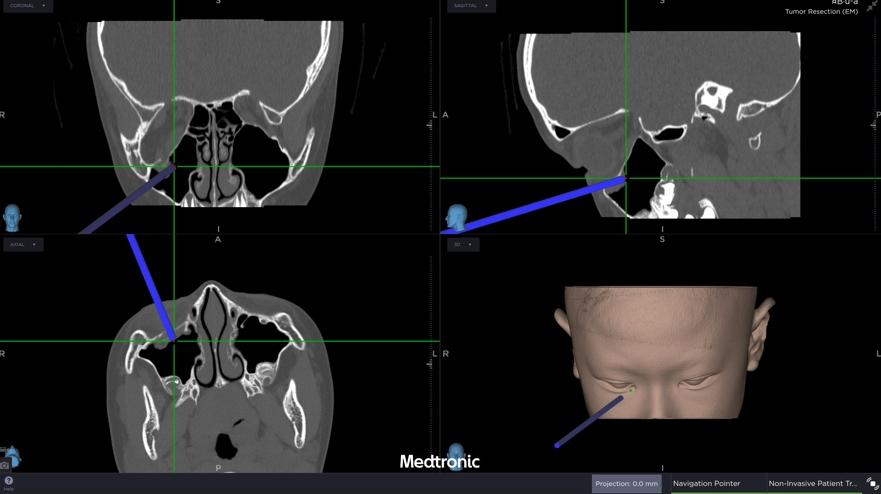

經評估後,中山醫學大學附設醫院口腔顎面外科醫療團隊邱昱瑋主治醫師、張芳語主治醫師及洪珮瑄主治醫師,立即制定手術方案,運用創新電腦數位模擬技術,術中搭配內視鏡與精密導航系統,精準定位眼底嵌頓肌肉的位置,成功將被夾住的眼底肌肉復位。術後,患者複視症狀消失,眼球活動恢復正常,並未留下相關併發症,順利重拾日常生活與學習品質。

中山附醫口腔顎面外科張芳語主治醫師補充,重建受損眼眶骨在臨床上挑戰重重,包括手術視野狹小、骨頭型態複雜、手術精準度要求高,以及術後疤痕與外觀重建的考量,透過精準的數位導航技術,醫師團隊能克服這些困難,幫助患者安全恢復功能與外觀,重拾自信與生活品質。洪珮瑄醫師則強調,對於兒童患者而言,手術精準度與微創性格外重要,不僅要恢復功能,更要兼顧未來面容發育的完整性;該起案例不僅展現數位導航手術在顏面骨折治療上的價值,也提醒家長與學校,即便外觀無傷痕,一旦出現眼球運動受限或複視症狀,應立即就醫,避免錯過黃金治療期。